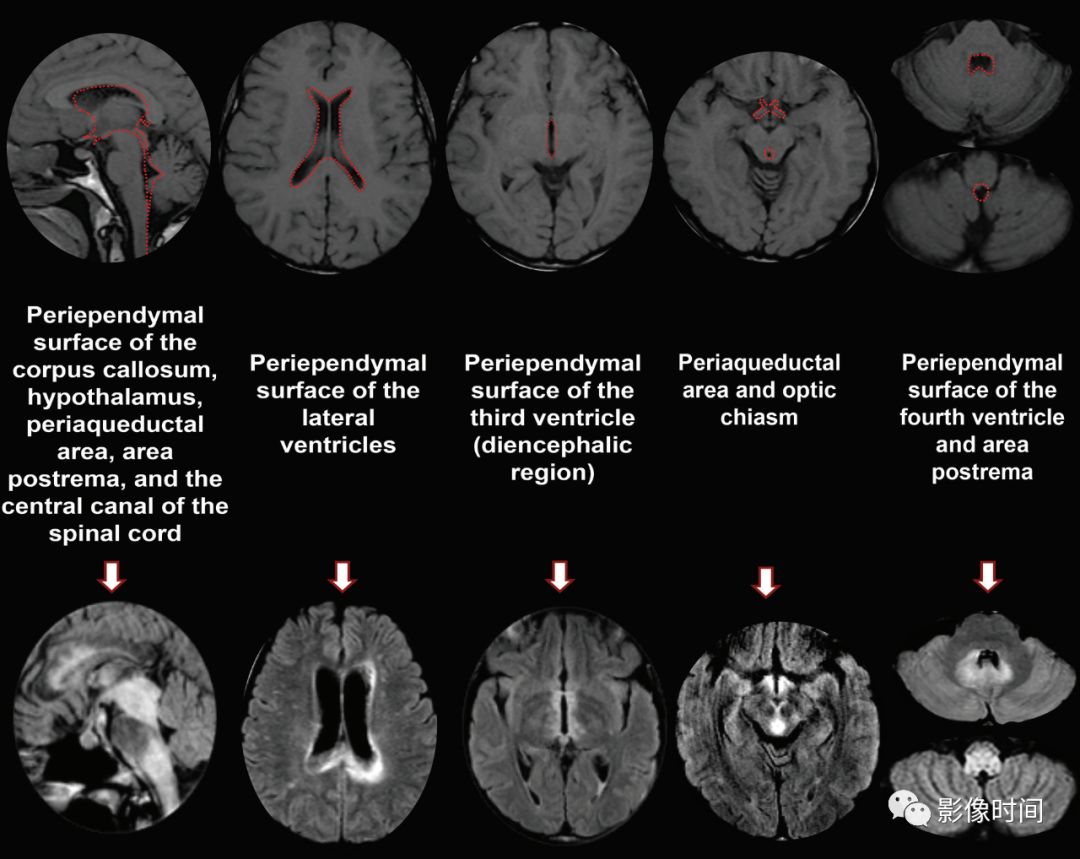

大脑:AQP4 通道是中枢神经系统最丰富的水通道,在室管膜周围、下丘脑和软脑膜下区以及脑干、极后区均有高表达。因此,高表达 AQP4 的特定区域成为 NMO 自身免疫靶点

后视路受累为主,明显强化